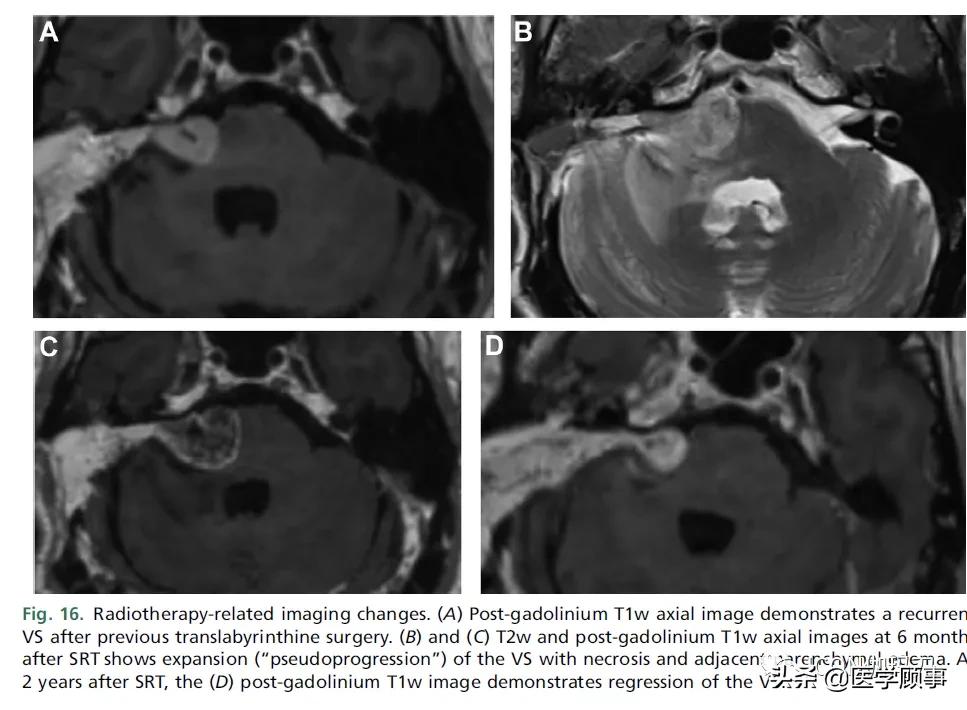

治疗前MRI主要需要用于肿瘤的轮廓勾画和计算准确的剂量体积直方图。使用三维T2w成像,有效的肿瘤分割现在已经被证明是可能的。一些影像学特征也可用于预测预后,保持的耳蜗CISS信号与听力保持有关,而一些纹理特征参数和较低的治疗前ADC值与放射治疗的反应有关。SRT后的预期变化包括暂时性增大,根据定义,25% - 60%的患者会出现这种情况。这不能被误解为肿瘤进展,因为只有一小部分增大的肿瘤出现了肿瘤进展。随后的肿瘤收缩通常在治疗后2年内发生,20 - 55个月后肿瘤体积缩小到小于原来的大小肿瘤肿胀通常与中央强化减弱(坏死)有关,但这与治疗的成功无关。放疗也可导致邻近脑实质信号改变(30%),通常会消退(图16)。尽管只有少数报道明确的良性VSs在放疗后变成恶性,但仍有人担心SRT会导致神经鞘瘤的恶性转变。

图16。放疗相关的成像变化。(A)钆剂后T1w轴位像显示既往经迷路手术后VS复发。(B)和(C) SRT术后6个月T2w和钆剂后T1w轴位图像显示VS扩张(假性进展),伴坏死和周围脑实质水肿。SRT后2年,(D)钆剂后T1w图像显示VS退缩。